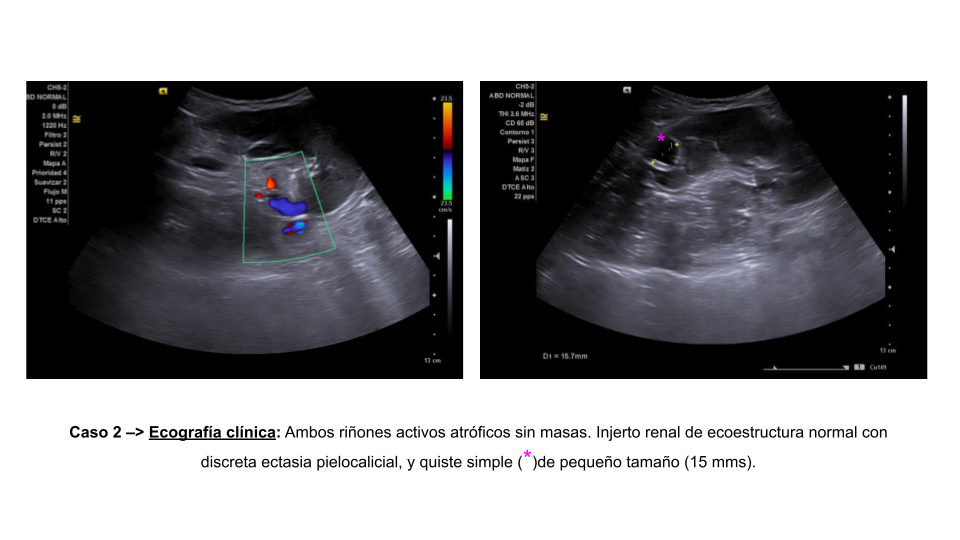

Se presentan dos casos clínicos sometidos a trasplante renal.

Ambos pacientes acuden a su seguimiento habitual.

Descripción de los hallazgos ecográficos y las imágenes más relevantes para la resolución del caso

Estos casos tienen en común: dilatación pielocalicial en los injertos renales postrasplante.

Revisando la literatura, la complicación urológica más frecuente es la ectasia pielocalicial (54% en algunos) y las fístulas urinarias; se producen por cambios en la vascularización tras manipular el injerto en la extracción y posterior trasplante. También puede estar relacionado con Tacrólimus (inmunosupresor).